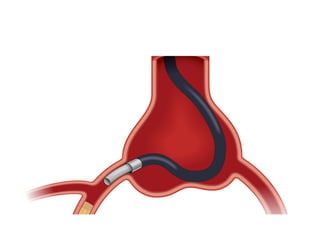

Anchoring balloon technique

• Described in 2003

(Fujita)

• Balloon inflated in a

non target side branch

vessel

• Advantages

– Guide catheter stabilization

(Anchor by guide wire)

– Penetration power of guide wire

– Cross of balloon cath or micro cath

– Sometimes preferable to extension

GC in some anatomy: very prox

CTO,right angle takeoff...

• Limitations

– If no anatomically accessible side

branch

– If branch used supplies collateral

flow (non distal visualisation,

ischemic risk)

– Risk of damage by the GC tip